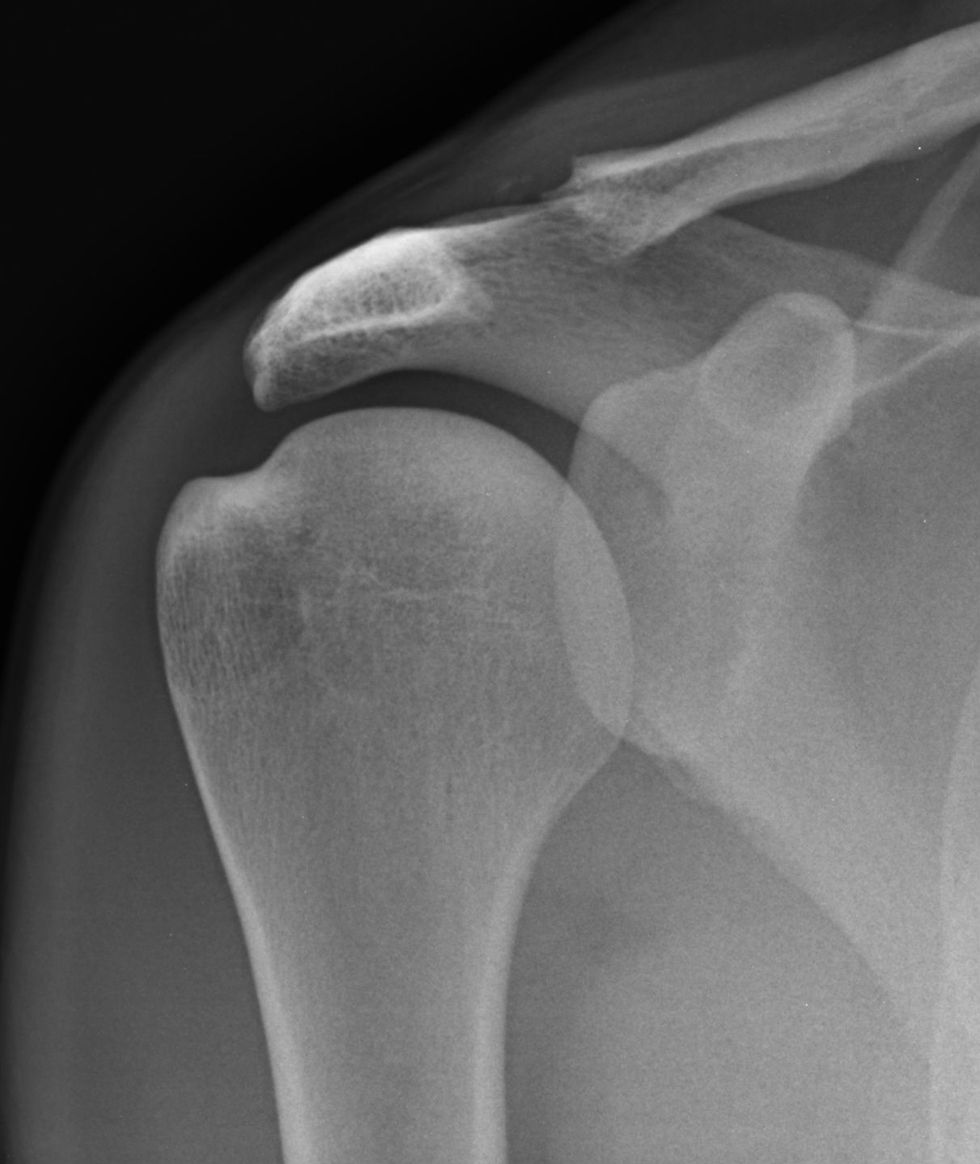

X-rays obtained at initial injury 8 months ago, reported as normal

Currently, repeat x-rays were performed and show the diagnosis

Radiographic findings suggestive of distal clavicular osteolysis include an eroded or worn appearance to the cortex of the bone.